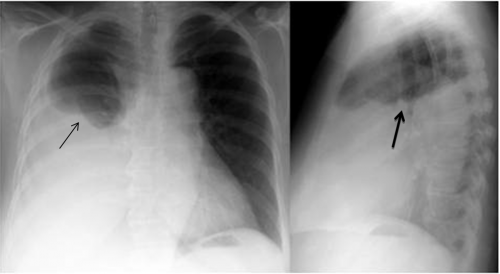

מבחינה קלינית חזה-דם מאופיין על-ידי החלשת קולות הנשימה, ועמימות בניקוש. בצילום חזה ניתן לראות עכירות המופיעה תחילה בבסיס הריאה ואחר כך גוברת והולכת. בשכיבה העכירות מתפשטת על פני כל הריאה, ובישיבה ניתן לראות פלס נוזל בחלק התחתון של הריאה (תמונה 10.16). ממצאים אלה נראים בבירור ב-CT חזה (תצלום 11.16).